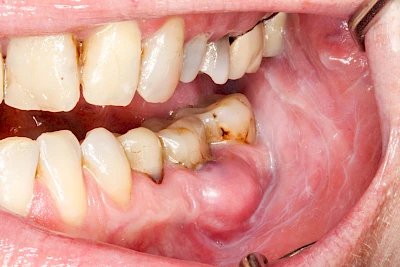

Sonderform: Abszess / Schwellung

Bei einem Abszess breiten sich Bakterien oder andere Erreger im Bereich der Kiefer und aufliegenden Weichteile aus, ohne gleich in die Mundhöhle durchzubrechen (siehe Fistel). Die schnelle starke Vermehrung und Einschmelzung von Bakerien und anderen Erregern führt zu einer meist sehr schmerzhaften und häufig sichtbaren Schwellung. Im weiteren Verlauf können Abszesse auch durch die Weichteile durchbrechen und Fisteln bilden. Zudem können im Kopf-Halsbereich Schwellungen (Ödeme) als sichtbares Zeichen der Körperabwehr auftreten.

Abszesse können, vor allem, wenn die Ausbreitung der Erreger im Körper über die Faszien und Logen voranschreitet, schnell zu einer Verschlechterung des Allgemeinzustands führen (z. B. Fieber) und sogar lebensbedrohlich werden. Deshalb ist sofort der Zahnarzt zu verständigen. Ist dieser nicht erreichbar, sollte der Notarzt gerufen werden.